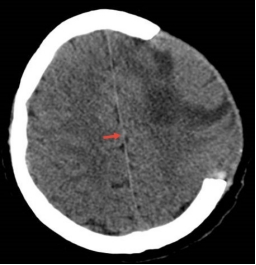

佩戴2周后硬膜下积液消失